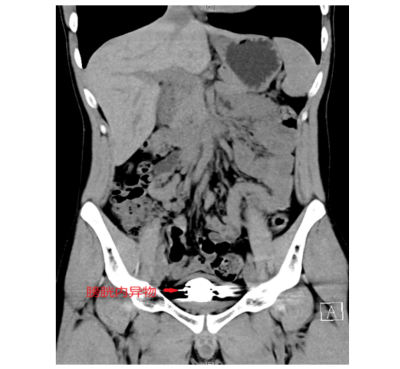

据了解,22岁的简轩(化名)因尿频、尿急、尿痛持续一年,近期症状加重才前往长沙中心医院(南华大学附属长沙中心医院)泌尿外科就医,经影像学检查发现,其膀胱内竟积聚大量直径约5毫米的金属圆珠,排列紧密且表面已形成钙化外壳。该院泌尿外科一区主任傅发军及其团队结合病史及临床经验判断异物为数十颗磁性钢珠,如不及时取出,长期滞留可能导致尿路梗阻、感染甚至组织损伤。

由于异物数量多、磁性强且表面光滑,传统开放手术创伤较大,团队研究后决定采用“经尿道膀胱镜钬激光碎石取异物术”。手术需克服三大难点:磁珠相互吸附难以分离、表面光滑不易抓取、膀胱壁脆弱易损伤。医疗团队通过精准影像定位和精细操作,历时2小时成功取出全部异物,共计50颗磁性钢珠。术后患者症状立即缓解,恢复顺利。